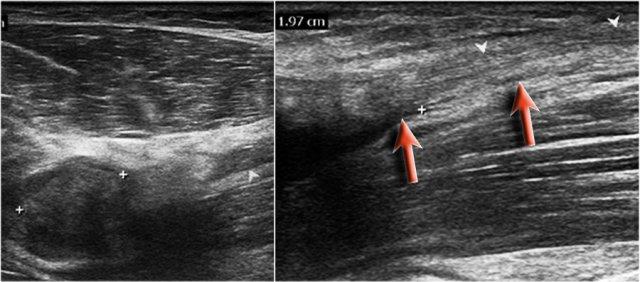

Đây là hình ảnh siêu âm của một nam giới 73 tuổi, xuất hiện đau đột ngột và cảm giác rách khi nâng một hộp đồ.

Có đau khi sấp và ngửa cẳng tay, ấn đau ở phía trước gần khớp khuỷu.

Không có bầm máu hay khối u sờ thấy được.

Trên hình ảnh mặt phẳng đứng dọc, gân bị dày lên, nhưng ở phần xa gân không còn hiển thị.

Đã thực hiện kiểm tra MRI.

Bây giờ hãy xem các hình ảnh MRI và cố gắng xác định xem gân có bị co rút không và liệu đó là rách một phần hay rách hoàn toàn…

Trên hình ảnh mặt phẳng đứng dọc, có vẻ như gân bị đứt hoàn toàn, nhưng hãy tiếp tục xem các hình ảnh tiếp theo.